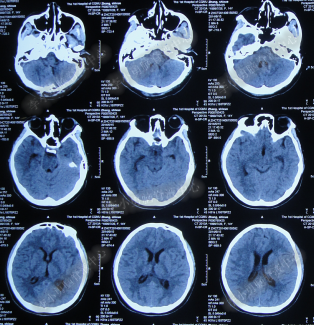

患者因恶心、呕吐伴头痛头晕,自行服药后无法自行缓解,于2014年5月29日就诊位于重庆的著名的三甲肿瘤医院,查全脑CTA和CT后诊断为“小脑蚓部占位伴幕上脑积水”(图-1、图-2)。

图-2:2014年5月29日头部CT